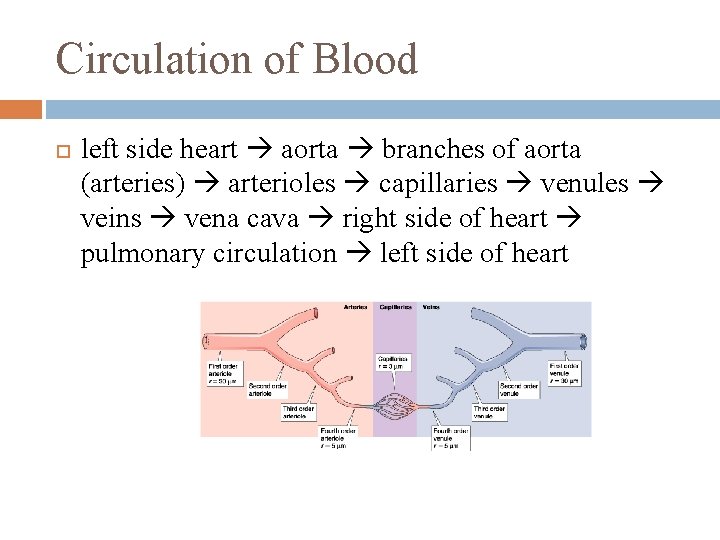

Circulation of Blood left side heart aorta branches of aorta (arteries) arterioles capillaries venules veins vena cava right side of heart pulmonary circulation left side of heart